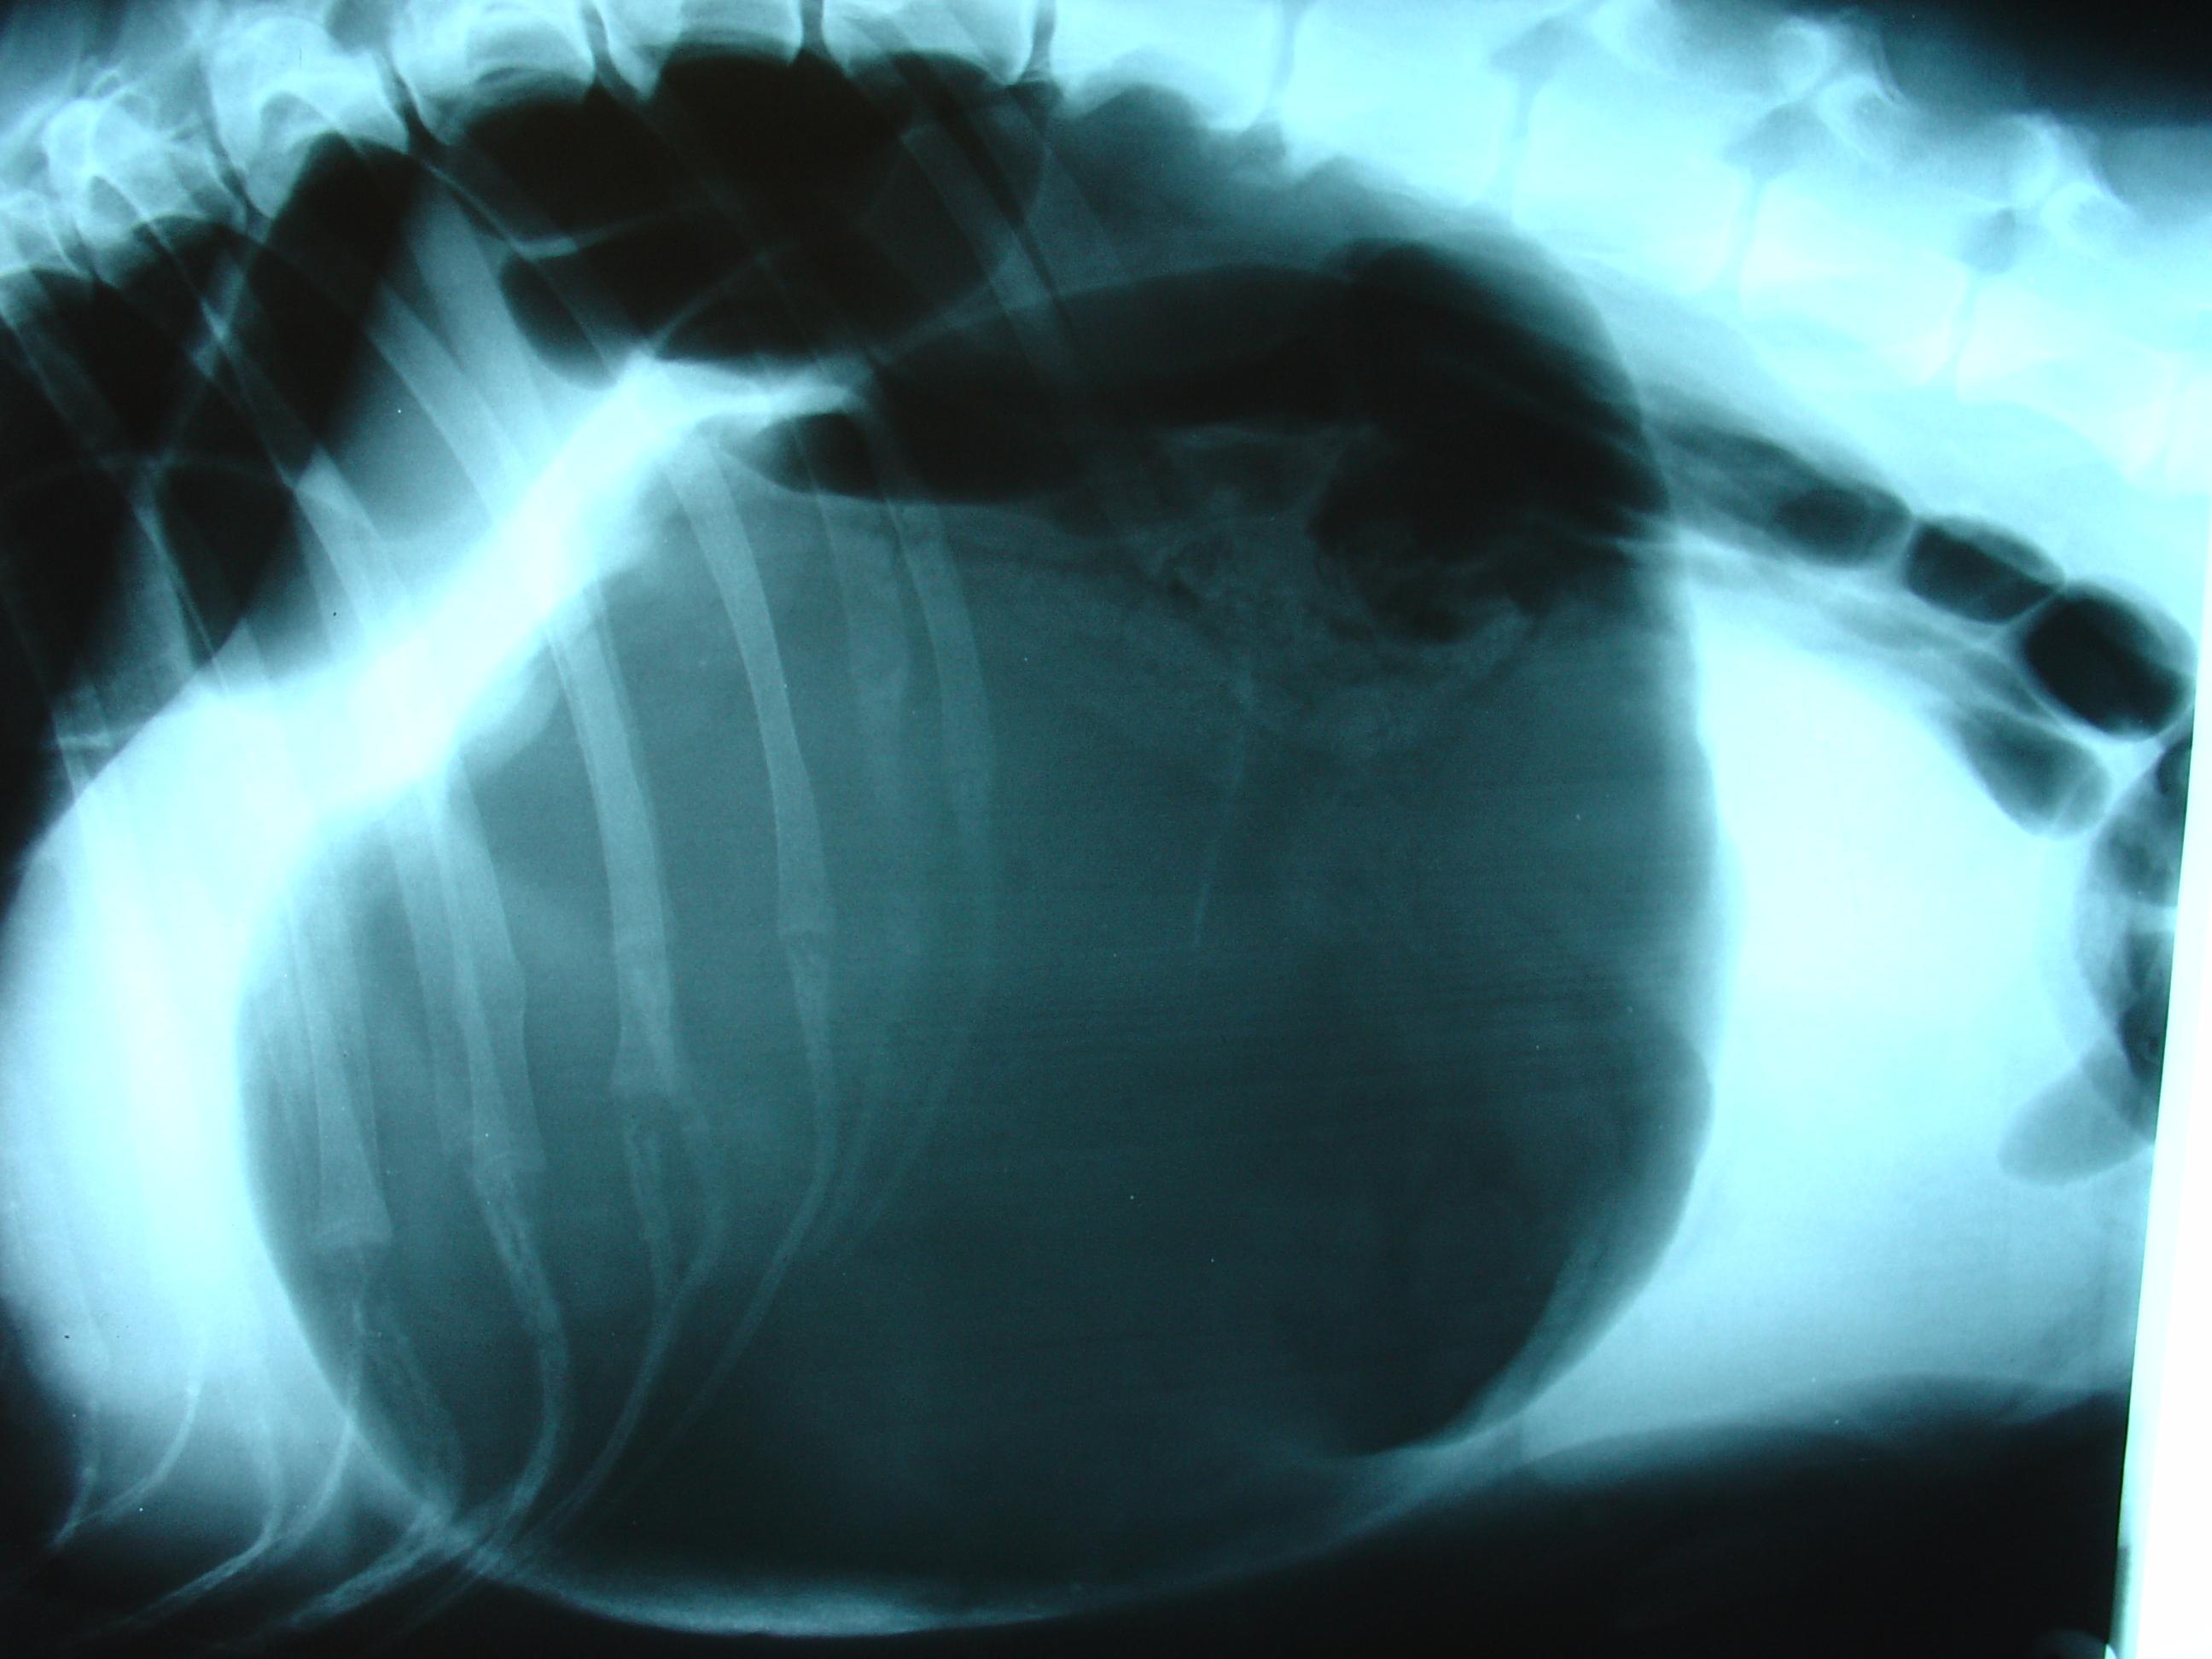

También se suelen hacer radiografías para confirmar este diagnóstico. La radiografía permite ver con claridad si el estómago está distendido o no. Además, si el estómago se ha girado, el píloro (orificio que conecta el estómago con el intestino) se observa desplazado con respecto a su posición normal.

Hola tengo una mestiza de galgo madre con sharpei padre tiene pecho profundo va a cumplir 5 años. Está bien de peso come gastrointestinal normal se le hizo hace un año RX el estómago estaba bien pero tiene gastritis y por momentos se estira cuello hacia arriba patas delanteras estiradas y se escucha un ruido como de tragar.el veterinario no me da respuesta a eso....por favor es mi vida y la cuido más que a mí yo soy sola con discap motora esta foto es de hace más de un año pero para que se vea cavidad torácica pronunciada a pesar de ser mediana (18,7 kg)